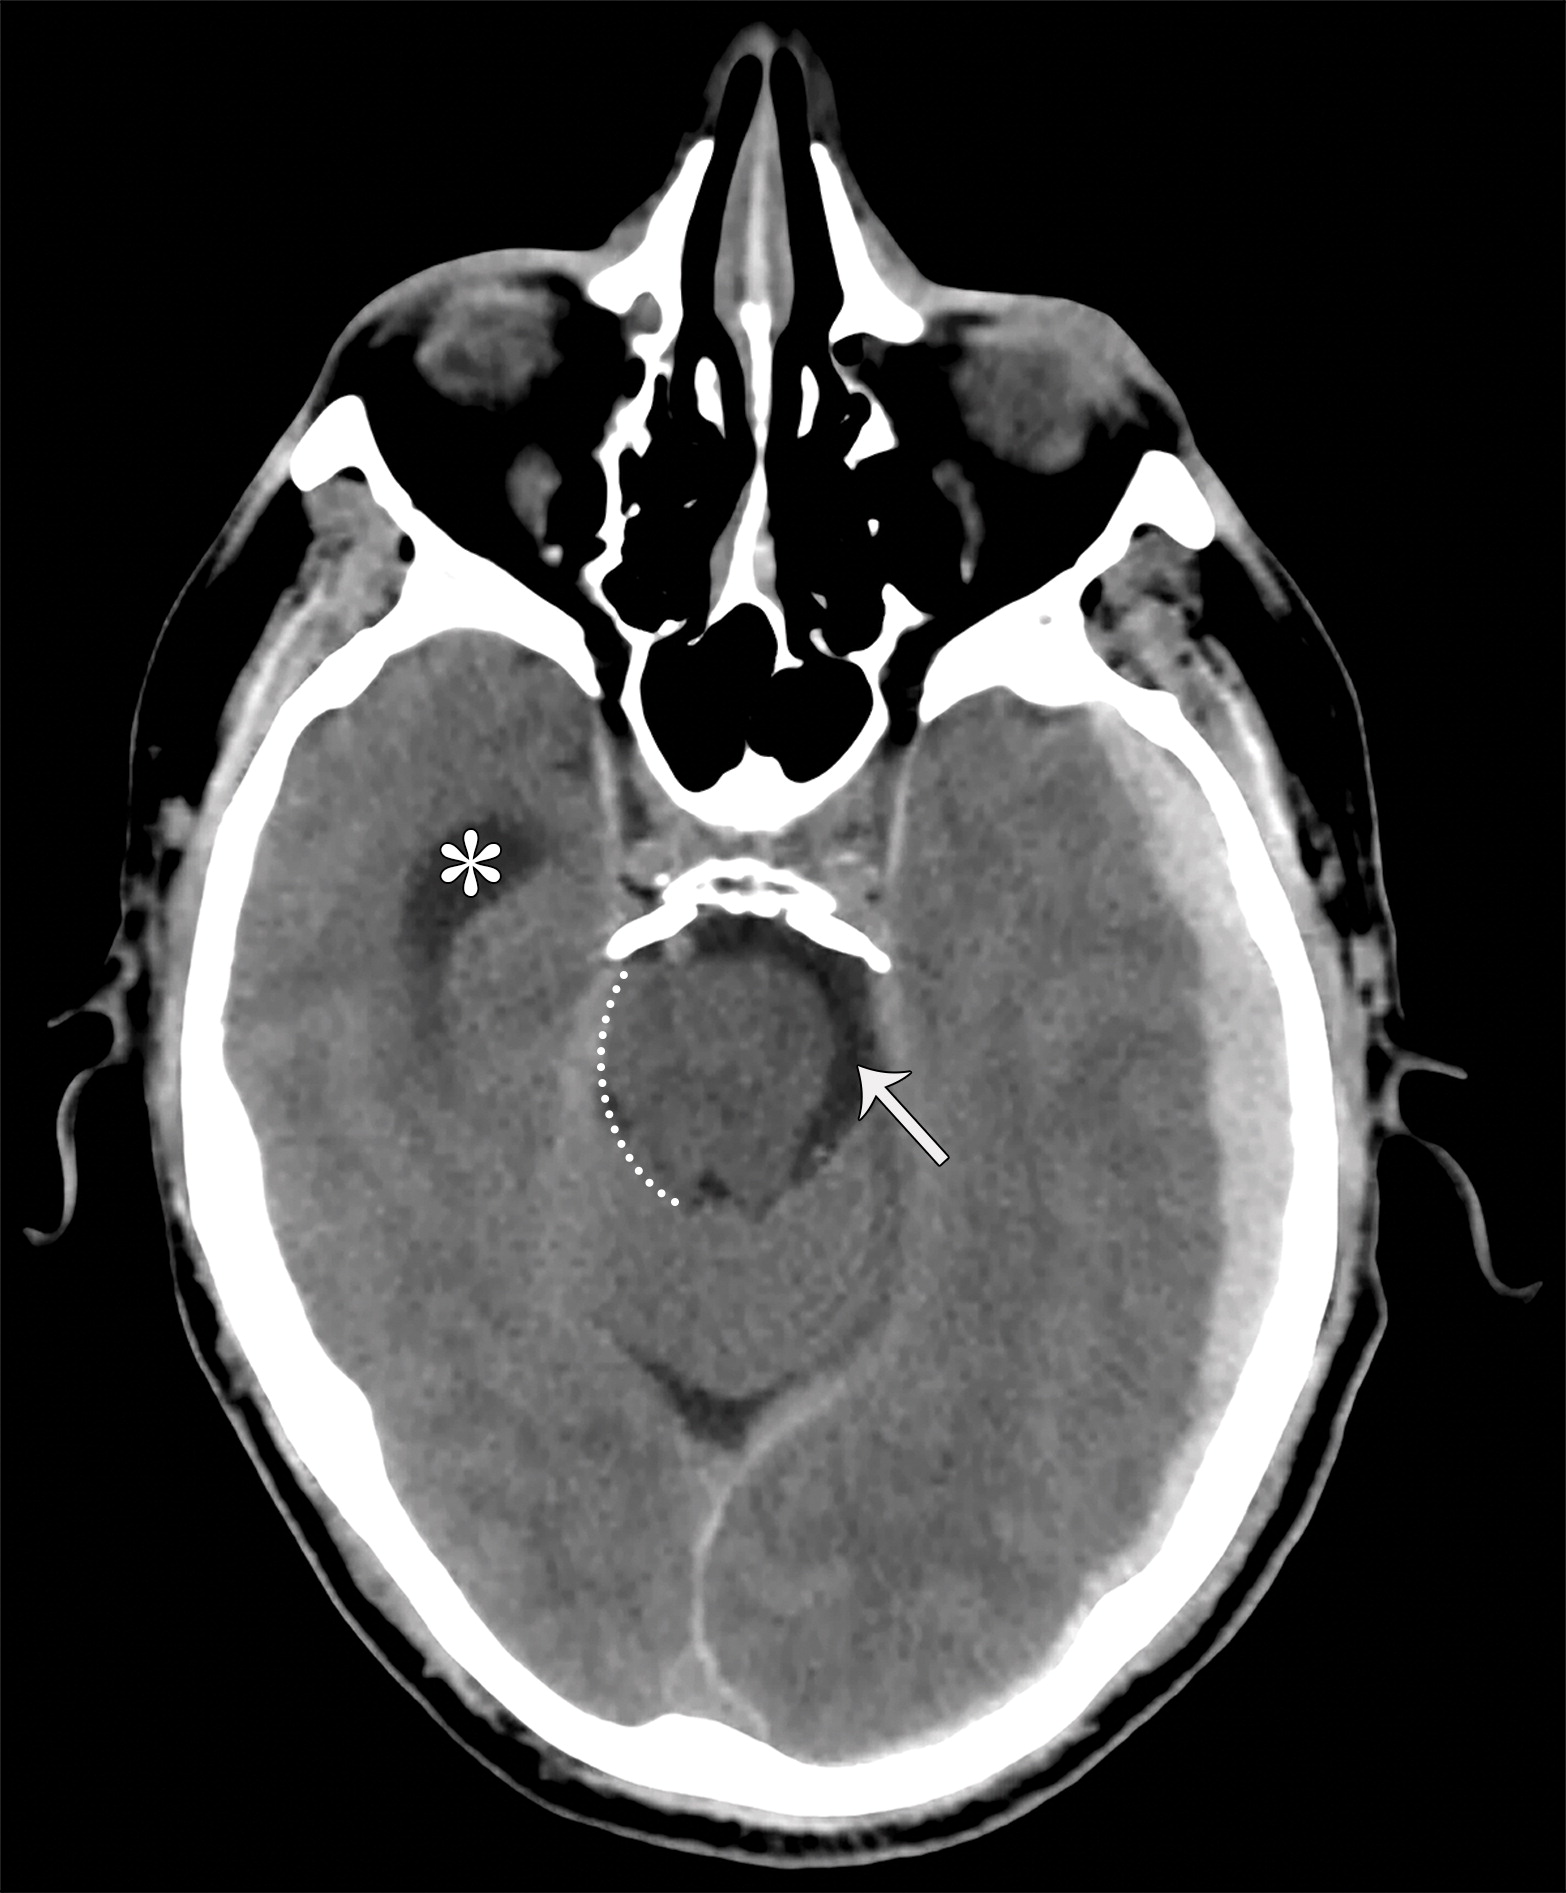

大脑镰下疝。平扫轴位CT示:右侧硬膜下血肿(*)伴混合密度影,表明处于不同时期的血液,血肿推挤使透明隔相对于中线(白色虚线)向左侧移位(白色长箭头)。右侧侧脑室受压,但是左侧侧脑室扩张。

下降性小脑幕裂孔疝。中脑受压,旋转,变长(白色短箭头)。中脑周围池完全闭塞。注意对侧侧脑室的增宽(*)。